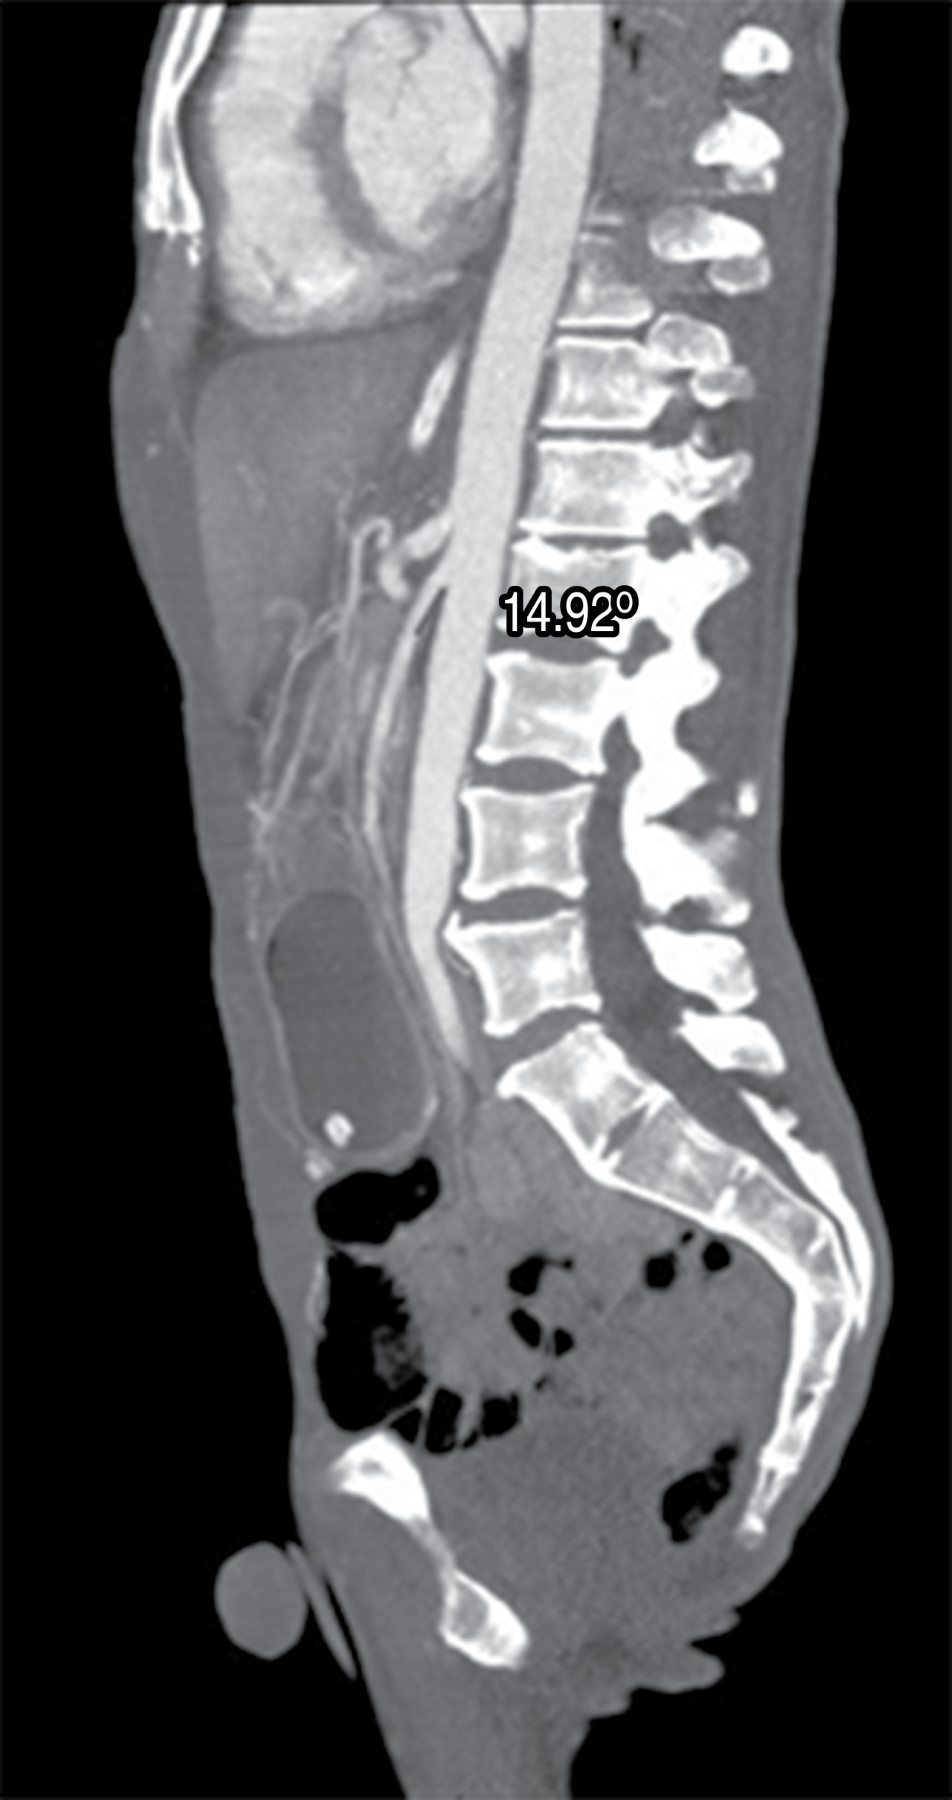

Se realizó tomografía de abdomen en la que se identifica dilatación gástrica con pérdida de los pliegues gástricos así como disminución de la distancia entre la arteria aorta y arteria mesentérica superior, la cual mide 8.05 mm (Figura 1). En el corte sagital de la tomografía se observa un ángulo agudo aortomesentérico de 14.92o (Figura 2). Desde su ingreso recibió manejo con descompresión gástrica con sonda nasogástrica, reposición hidroelectrolítica, analgésicos y antibioticoterapia con cefalosporinas de tercera generación; sin embargo, persiste la obstrucción a pesar de manejo conservador durante 48 horas, por lo que se propone y acepta manejo quirúrgico. Se realiza abordaje laparoscópico con cinco puertos, se moviliza el colon transverso y se visualiza el sitio de obstrucción secundaria a pinzamiento de la arteria mesentérica superior entre la tercera y la cuarta porción del duodeno. Se realiza duodenoyeyuno-anastomosis mecánica a 60 cm del ligamento de Treitz, se cierra gastroenterotomía en dos planos con monofilamento de absorción lenta para el primer plano y no absorbible para el segundo. Con buena evolución postoperatoria, inicio de líquidos a las 24 horas y progresión a dieta blanda a las 48 horas. Fue egresado por mejoría 48 horas después del procedimiento. En seguimiento postquirúrgico durante dos meses con adecuada tolerancia a la vía oral, no se cuenta con secuencia clínica posterior, ya que el paciente no asiste a control.

Figura 2